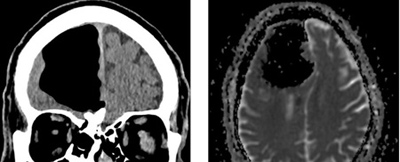

تصاوير سی تی اسكن مغز بيماری که بخش بزرگی از لوب پيشانی راست مغزش ناپديد شد

براساس گزارش ساينس الرت، تصاوير سی تی اسكن مغز اين بيمار نشان داد بخش بزرگی از لوب پيشانی راست مغز مرد ناپديد شده است.

نتيجه سی تی اسكن گيج كننده بود، حفره ای بزرگ و سياه به وسعت 9 سانتيمتر در لوب پيشانی سمت راست مرد ديده می شد. در مرحله بعدی مغز مرد با دستگاه MRI مورد بررسی قرار گرفت و پزشكان دريافتند ماده مغزی در جمجمه بيمار ناپديد نشده است، بلكه درون جمجمه اش حفره ای از هوا به نام پنوماتوكوئل ايجاد شده بود كه معمولا در بيمارانی ديده می شود كه دچار آسيب ديدگی صورت يا عفونت تنفسی شده اند يا در جمجمه آنها جراحی انجام شده است.